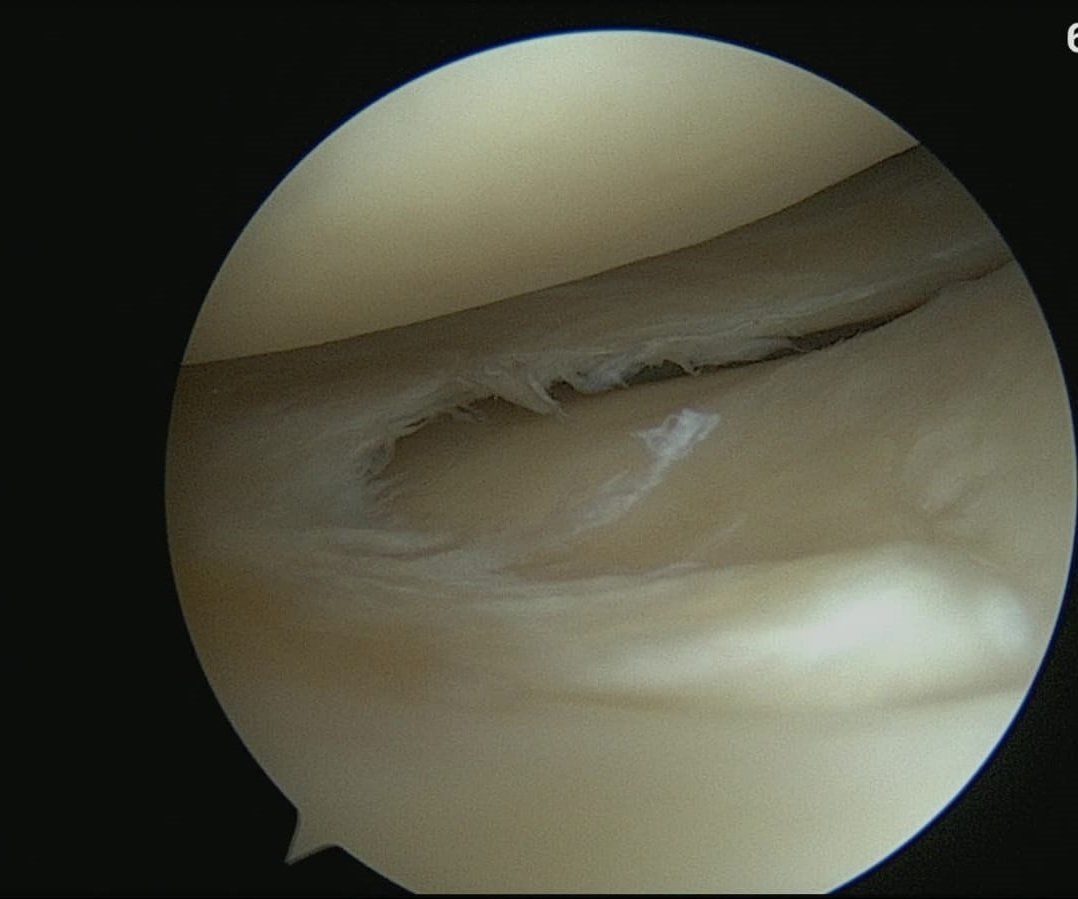

Lesioni osteoarticolari

Le lesioni osteoarticolari derivano da traumi quali lussazioni, fratture, distorsioni, contusioni o tendiniti che a loro volta causano l'usura delle cartilagini o il deterioramento dei tendini ; le più comuni riguardano il gomito, il polso, l'anca, la spalla, il ginocchio e la caviglia specialmente se il soggetto colpito pratica attività sportiva.